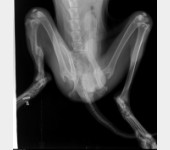

Leoś przebywał długie lata w schronisku w Raciborzu. Nikt Leosia nie chciał adoptować , taki był wycofany , bał się ludzi a w szczególności mężczyzn , co sami na sobie odczuliśmy jeżdżąc na wizyty zapoznawcze do hotelu w Gliwicach gdzie został przetransportowany. Leoś skradł nasze serca. Pomimo nie małych wątpliwości podjęliśmy decyzję o adopcji Leona i to była najlepsza decyzja. Leoś to piesek o wspaniałym charakterze , zrobił bardzo duże postępy , bez nas nigdzie się nie ruszy. Jesteśmy zmuszeni prosi o pomoc. Niestety okazało się , że nasz pupil zaczął mieć problemy z chodzeniem. Diagnoza lekarska była jednoznaczna, bez operacji Leoś przestanie chodzić. A opis lekarza ortopedy brzmiał tak : CAŁKOWITE ZWICHNIĘCIE STAWÓW NADGARSTKOWYCH , CAŁKOWITE ZERWANIE WIĄZADEŁ , DAWNE ZŁAMANIE KOŚCI PISZCZELOWEJ Z NIEPRAWIDŁOWYM ZROSTEM. LICZNE ZWYRODNIENIA STAWÓW, Załączam zdjęcia RTG .

Obecnie Leoś jest po operacji łapy przedniej lewej co ilustrują zdjęcia.

Dzis Leos jest już po operacji drugiej przedniej łapki. Wszystkim i z osobna dziękujemy za wsparcie. Podczas wizyty okazało się, że Leos musi mieć operacje na dwie tylne łapki. Koszt operacji to około 2500zl. Załączam opis ortopedy.